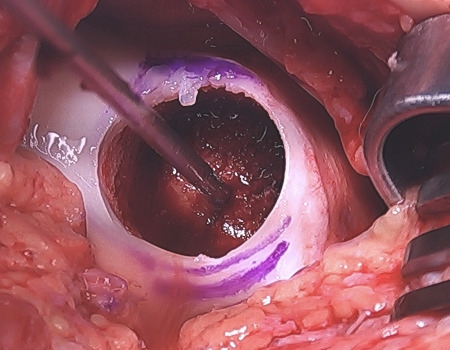

Coring Out of Recipient Site

Cored Recipient Trochlear Site